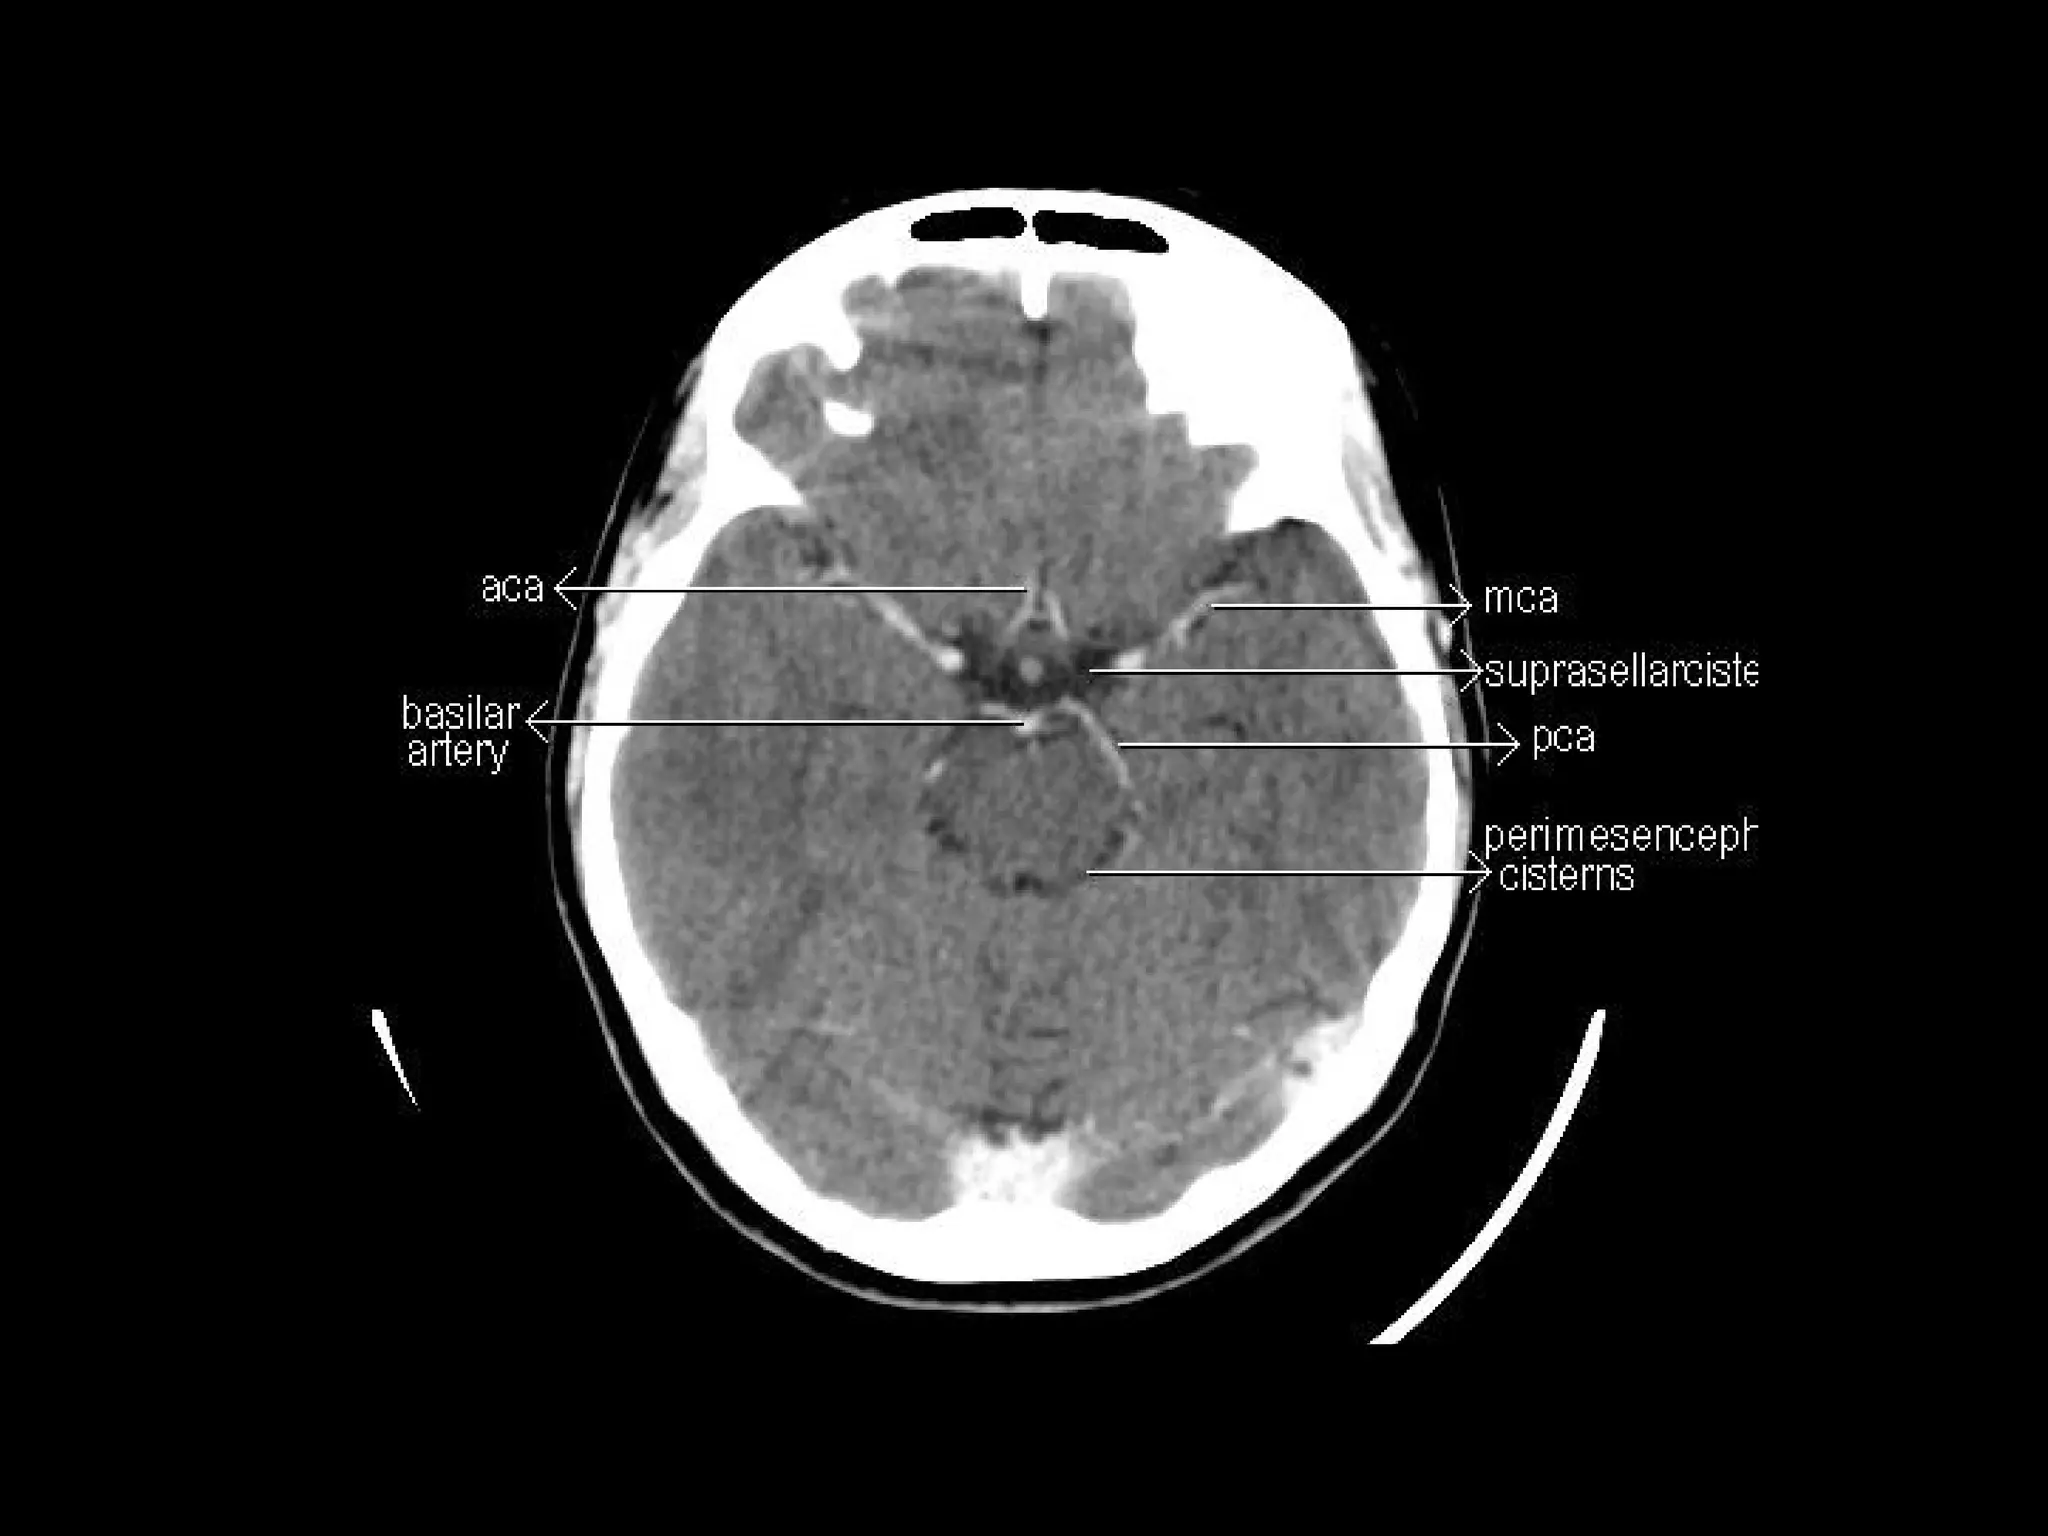

Radiographers are medical professionals who perform diagnostic imaging examinations and procedures to help physicians diagnose and treat diseases. They work under the supervision of radiologists to operate X-ray, CT, MRI, ultrasound and other medical imaging equipment and must have a strong understanding of human anatomy and pathology. Radiographers are responsible for correctly positioning patients, ensuring proper imaging techniques are used, and evaluating the quality of the resulting images.